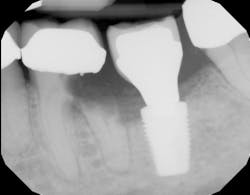

- Labialization of the dental implant, especially in the maxillary anterior region (figure 1)

- Thinning of the hard and soft tissues around the dental implant (figure 2), which can increase the risk of a failed implant if tissue support is compromised